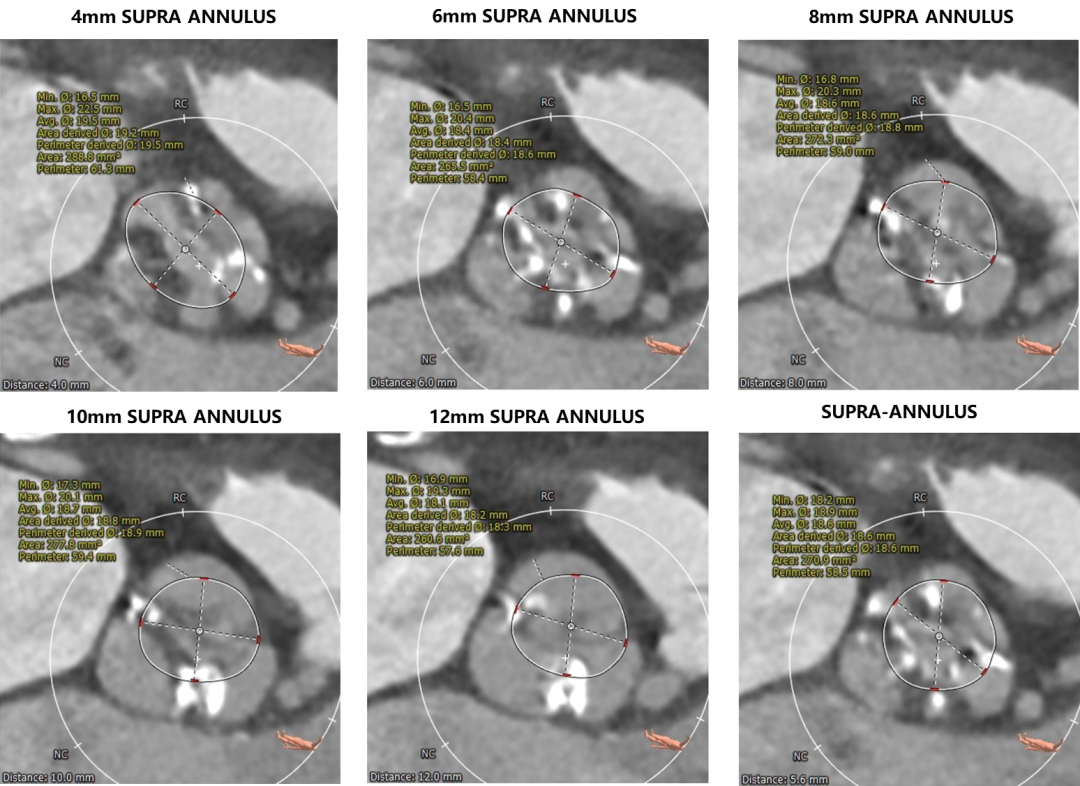

1.主动脉瓣瓣环周长77.8,平均周长径24.1。

2.主动脉瓣成三叶式,瓣叶增厚并伴有四级钙化,钙化分布不均匀,左无交界处钙化融合形似嵴并延伸至血管壁。

3.左右冠脉开口高度可,冠状动脉钙化严重。

1.瓣叶钙化并纤维化增厚对人工瓣膜形态存在影响,左无冠窦交界处钙化为根部最大影响因素。

2.根据CT分析钙化分布、瓣叶长度及瓦氏窦宽度预估左冠存在遮挡可能性。

主动脉根部评估:

瓣环上解剖结构评估: